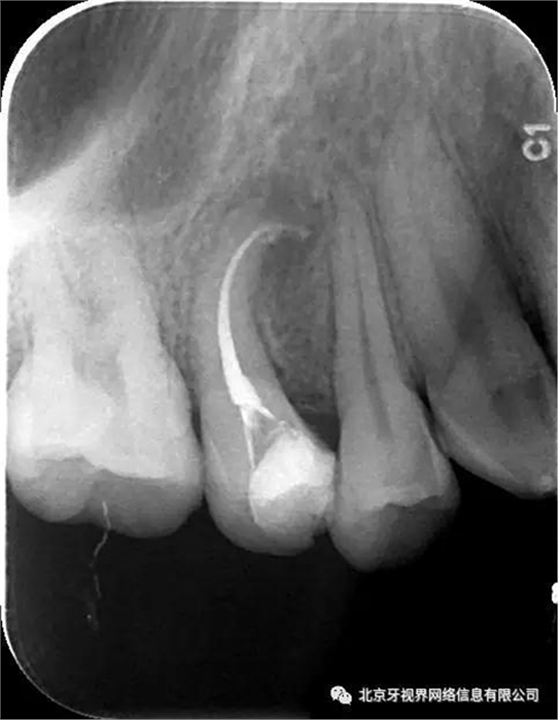

2次復診常規(guī)根備加根充(AH-plus糊劑加牙膠尖根充)

最后附帶近期彎曲根管的圖片